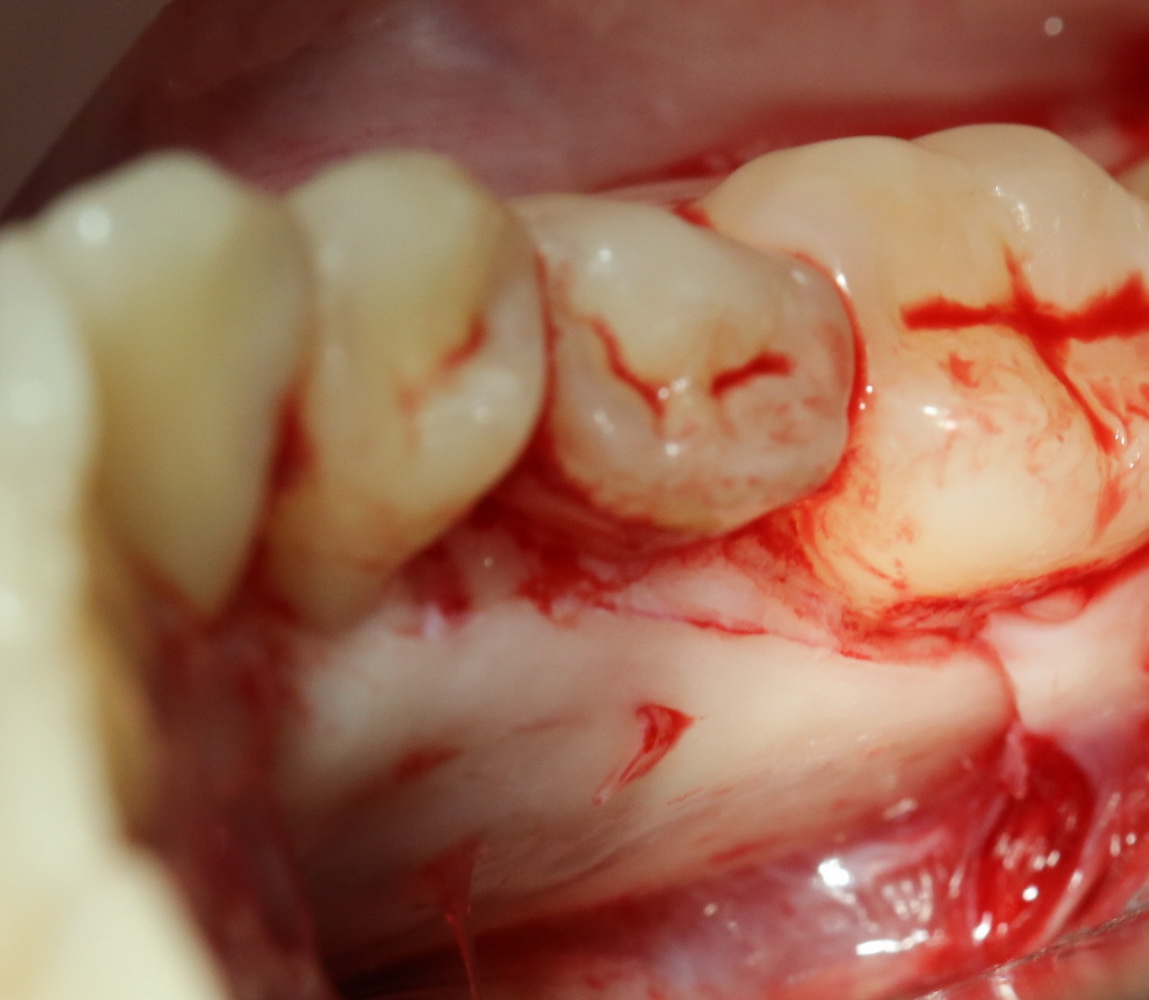

Теперь аккуратно нам нужно выделить сами зубы:

А вот они! Далее мы руководствуемся главным правилом хирурга-стоматолога:

При удалении зубов нельзя прилагать значительных физических усилий. Если операция идет правильно, зубы должны, вообще, сами вываливаться из лунок.

Однако, наши сверхкомплектные зубы вываливаться не хотят. Потому что их коронки образуют что-то вроде клина, который непросто вытащить через маленькое трепанационное отверстие.

Поэтому мы, всё также, с помощью ультразвука, отпиливаем коронку одного из зубов:

После чего, зубы вываливаются из лунок самостоятельно. В прямом смысле слова: